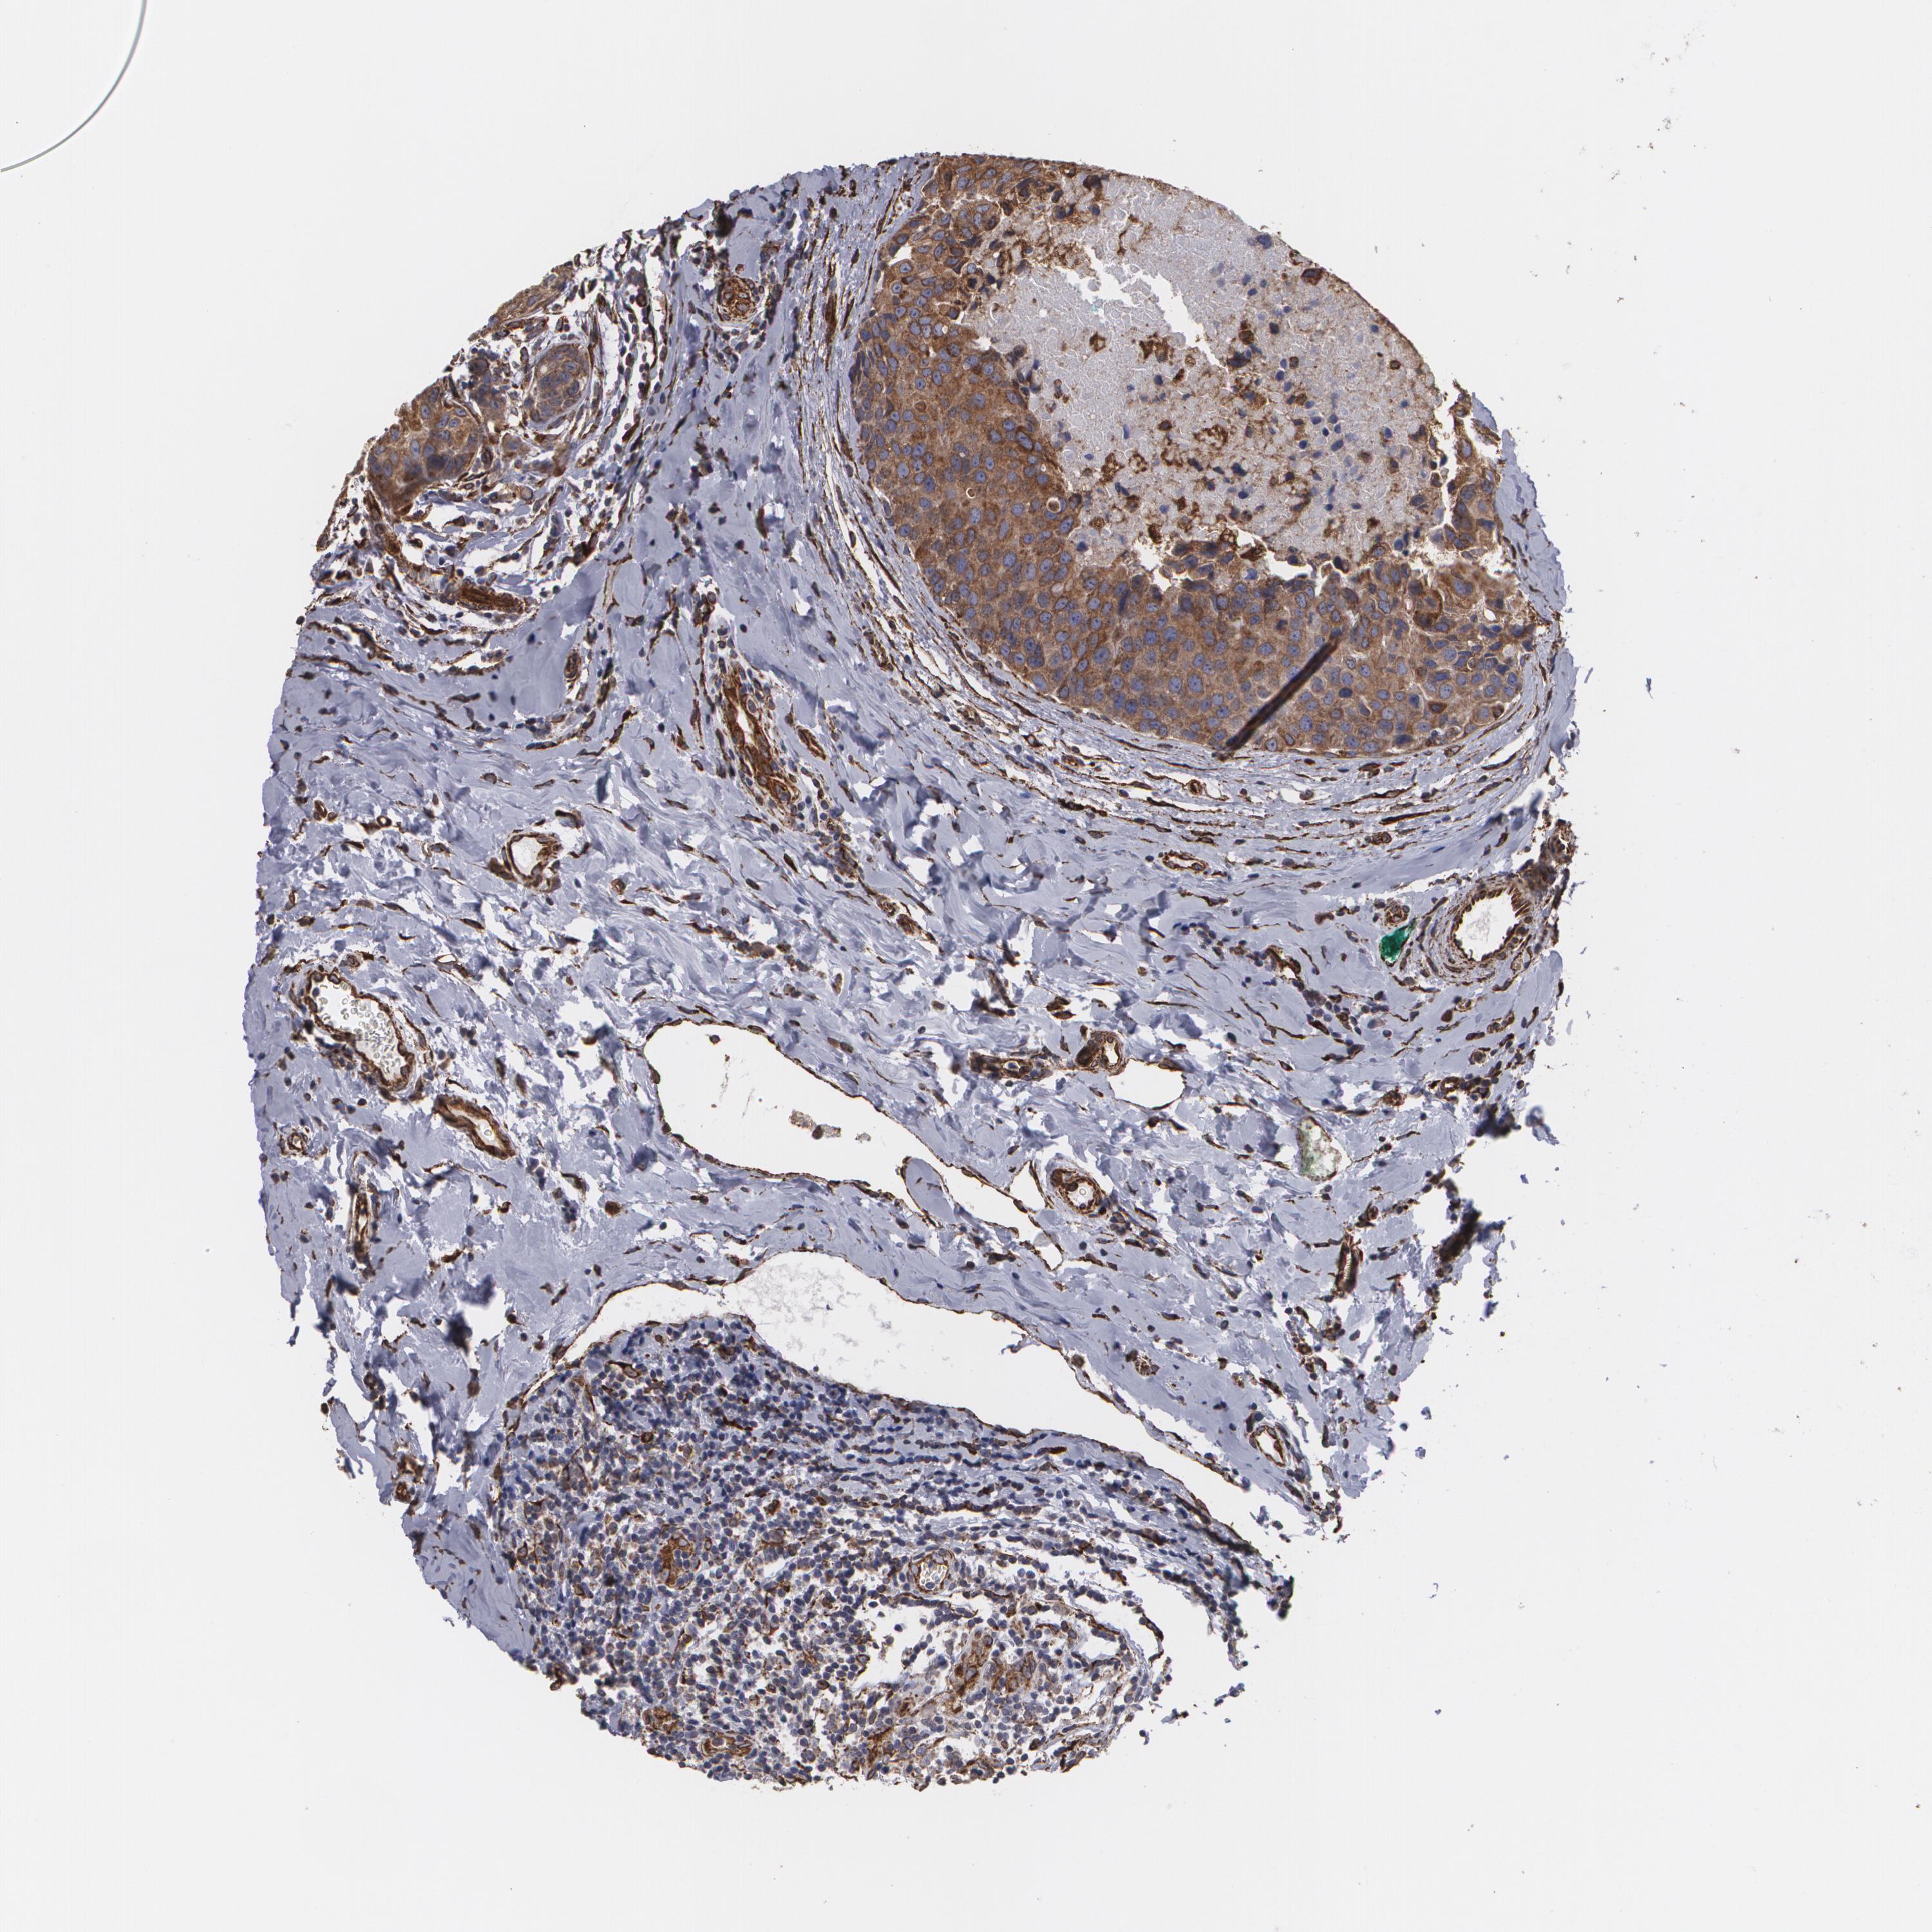

CYB5R3

CANCER BREAST CANCER Show tissue menu

BRCA TCGA BRCA VALIDATION PROTEIN EXPRESSION

Breast cancer

Human cancer

Breast invasive carcinoma